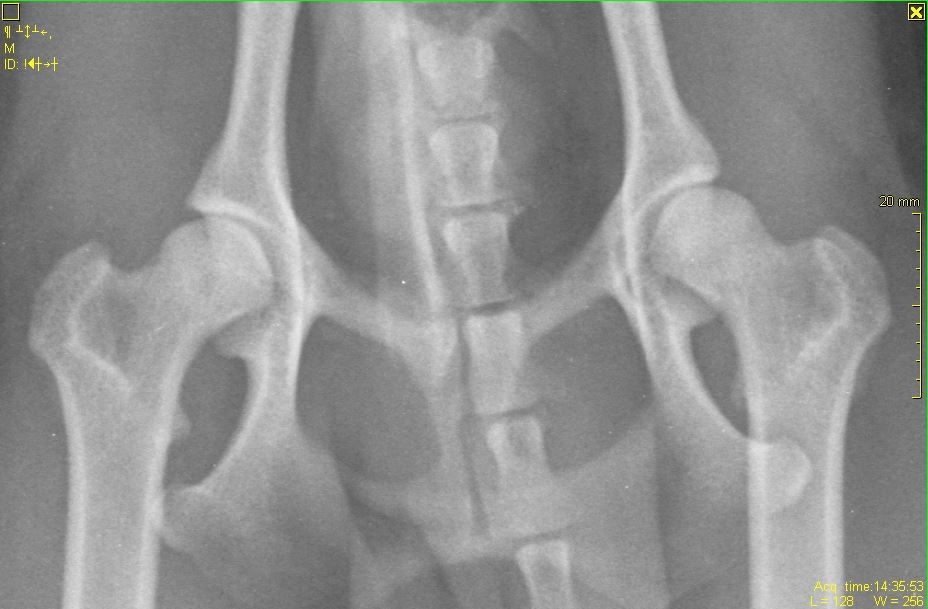

На выходных ездили в вет.клинику, при первичном осмотре врач-хирург поставил предварительный диагноз - дисплазия тазобедренного сустава, отправили нас на снимок, чтобы посмотреть, в каком состоянии головка бедра... После того, как сделали снимок, был поставлен окончательный диагноз - врожденный вывих тазобедренного сустава...

Прикладываю снимки, приблизила, чтобы лучше видно было. Также выкладываю снимок грудной клетки(этот снимок мы делали пару месяцев назад, когда он кашлял и врач исключал бронхит), на нем тоже есть ТБС, вдруг тоже на нем что-нибудь видно..

А где вы вывих тбс видите на снимках? И какой связки там нет?

В том то и дело, что я вывиха не вижу... Потому и сомневаюсь... пересмотрела наверное больше сотни разных снимков собак с вывихами, дисплазиями и другой ерундой, но на нашем снимке головка бедренной кости находится в вертлужной впадине, никаких наростов на ней нет, сама вертлужная впадина выглядит как глубокая чашка, а не как блюдце (которое описывают при дисплазии).. Потому и сомнения:(((

Если врач реально сказал то, что вы пишете - сходите к другому и проверьте колени (хотя по снимку и так видно)

По сабжу. Переделывайте рентген - собака лежит как черти что. Должна лежать прямо. Конечности должны быть строго параллельны, рентген ТБС делается с оттяжкой. Тогда можно будет говорить о корректных снимках (и только о них). О каких связках речь, если они на рентгене не видны? Для того, чтобы разглядеть связки вообще - делают КТ либо МРТ.

В любом случае вывиха тбс там нет. Зато отсняли во всех проекциях, вплоть до грудной клетки))) врач выполнял план по рентгену? Либо тс нам что-то не договаривает

именно вывих, но коленной чашечки.

Даже при этой раскладке явно видно, что вывиха тбс нет.

Под наркозом и правильная раскладка важны при постановке дисплазии и Ее степени.